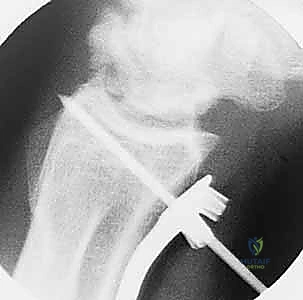

- الأشعة السينية (X-Rays): وهي الخطوة الأولى. تساعد الأشعة السينية في رؤية التغيرات في كثافة العظم الهلالي (المرحلة الثانية)، أو رصد أي انهيار في العظم (المرحلة الثالثة)، وكذلك تقييم طول عظمي الكعبرة والزند لاكتشاف وجود "تباين زندي سلبي".

- التصوير المقطعي المحوسب (CT Scan): يُستخدم أحياناً للحصول على صور ثلاثية الأبعاد وعالية الدقة للعظم الهلالي لتقييم مدى الانهيار والتفتت بدقة بالغة، مما يساعد الدكتور هطيف في التخطيط الجراحي الدقيق قبل العملية.